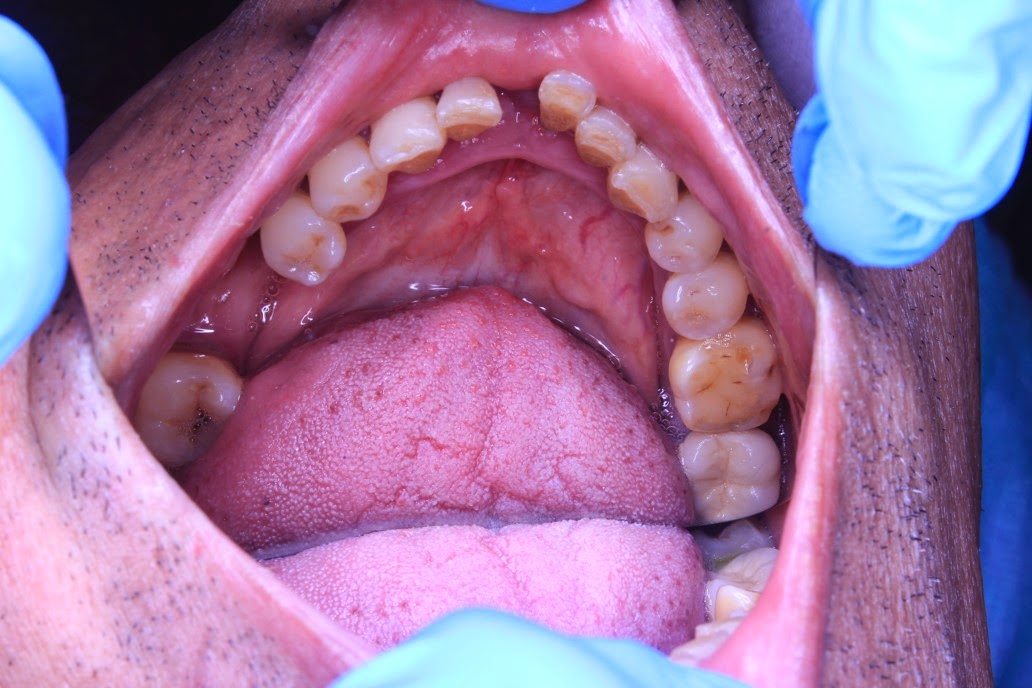

Occlusal View of the lower arch showing the missing teeth